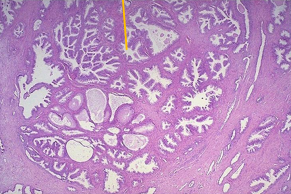

Hiperplasia fisiológica en glándulas endometriales